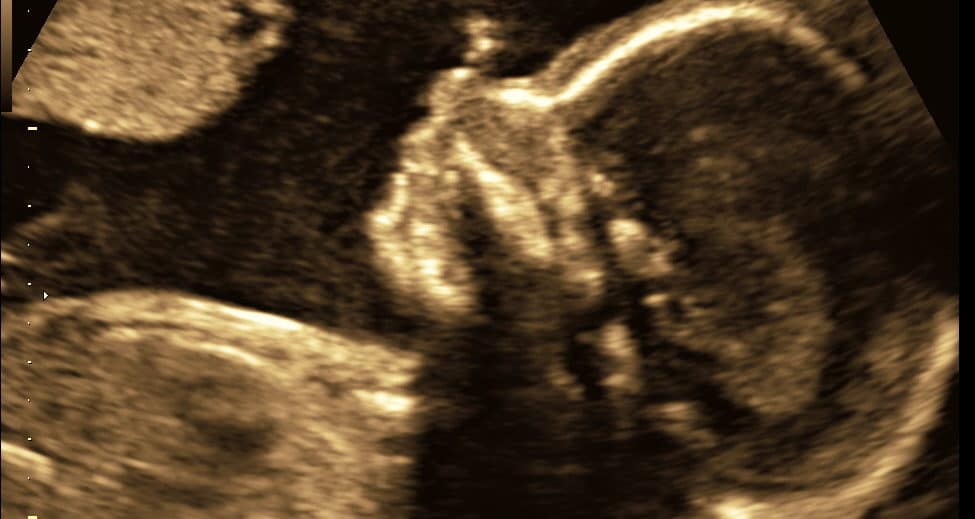

Acrania é uma anomalia fetal caracterizada pela ausência parcial ou total dos ossos do crânio. A condição é freqüentemente associada…